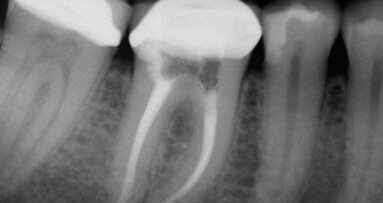

Rozpoznano: grupę II wg Majewskiego, grupę A3 wg Eichnera, a wg Galasińskiej-Landsbergerowej – klasę II zarówno w szczęce, jak i w żuchwie. W badaniu klinicznym wykazano nieprawidłowości, które w sposób istotny mogłyby wpłynąć na końcowy efekt leczenia i wymagały przygotowania ortodontycznego przed przystąpieniem do docelowej rekonstrukcji implantoprotetycznej. Pacjent został skierowany na konsultację do ortodonty, gdzie stwierdzono przedwczesną utratę zębów 14, 36, 46, zgryz urazowy tet-a-tet na 12, 42, szparowatość wtórną między 43 i 44 oraz 33 i 34, mezjoinklinację 15, 37, 47, asymetrię łuku górnego i dolnego, pogłębienie zgryzu, stłoczenie dolnych siekaczy niewielkiego stopnia oraz spłaszczenie kształtu łuku dolnego.

Założono 2 aparaty stałe (AS). Leczenie ortodontyczne trwało ok. 14 miesięcy. Po roku od rozpoczęcia leczenia założono implanty w miejsce brakujących zębów 14, 46 i 36. Implantację

wykonano zgodnie z ogólnie przyjętą procedurą, przy czym do implantów dokręcono

od razu śruby gojące (tzw. Gojenie otwarte). Po zdjęciu górnego AS pacjentowi przyklejono retainer 13-33 i wykonano płytkę Schwartza, którą miał użytkować do czasu wykonania odbudowy protetycznej. W łuku dolnym wykonano retencję stałą w odcinku 35-45. Wykonanie retencji skojarzono z osadzeniem implantokoron 36 i 46.